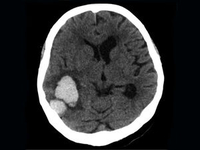

[ISC2017]脑出血后的缺血性脑卒中预防有了新选择?

对于既往有过脑出血或多发脑微出血的患者,缺血性脑卒中的二级预防是一个棘手的问题。近日,来自韩国的研究者纳入了数个亚洲国家及地区的患者,尝试使用西洛他唑进行二级预防,得到了喜人的结果。虽然这项研究的结论难以在世界范围内推广,但对于同为亚洲人群的我们,或许也能带来一些帮助。